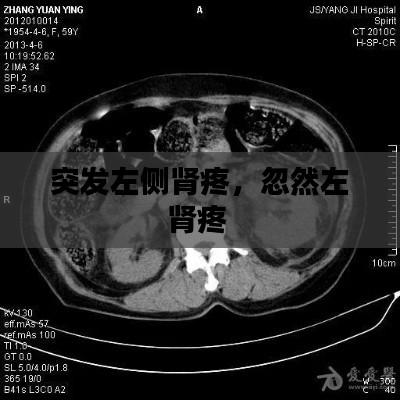

• 在医生的监督下进行必要的检查,如超声波、CT扫描或MRI,以确定疼痛的原因。